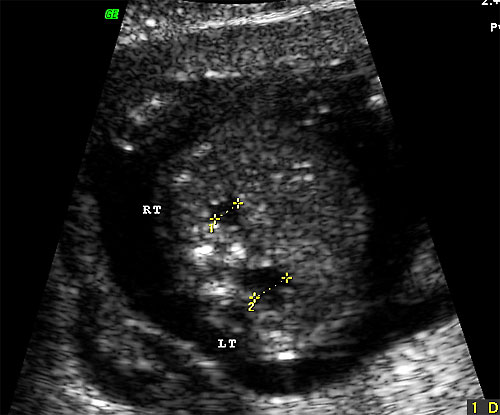

- Nuchal Skin Fold (Benacerraf BR, Frigoletto FD Jr, Laboda LA. Sonographic diagnosis of Down syndrome in the second trimester. Am J Obstet Gynecol. 1985 Sep 1;153(1):49-52)

- Midtrimester (16-22 weeks)

- Edematous integument, with or without fluid collection

- Cut-off value: 6.0 mm